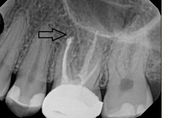

Upper molar failed root canal and apicoectomy:

3-month follow-upThis person presented with one root that had failed from root canal treatment. The arrow in the picture, shows the infection as well as extra filling material that was pushed out of the root. An apical microsurgery was performed using the laser. The infection and excess material was cleaned out. Complete healing is visible 3 months after. The tooth was saved. This is a poor area for an implant.